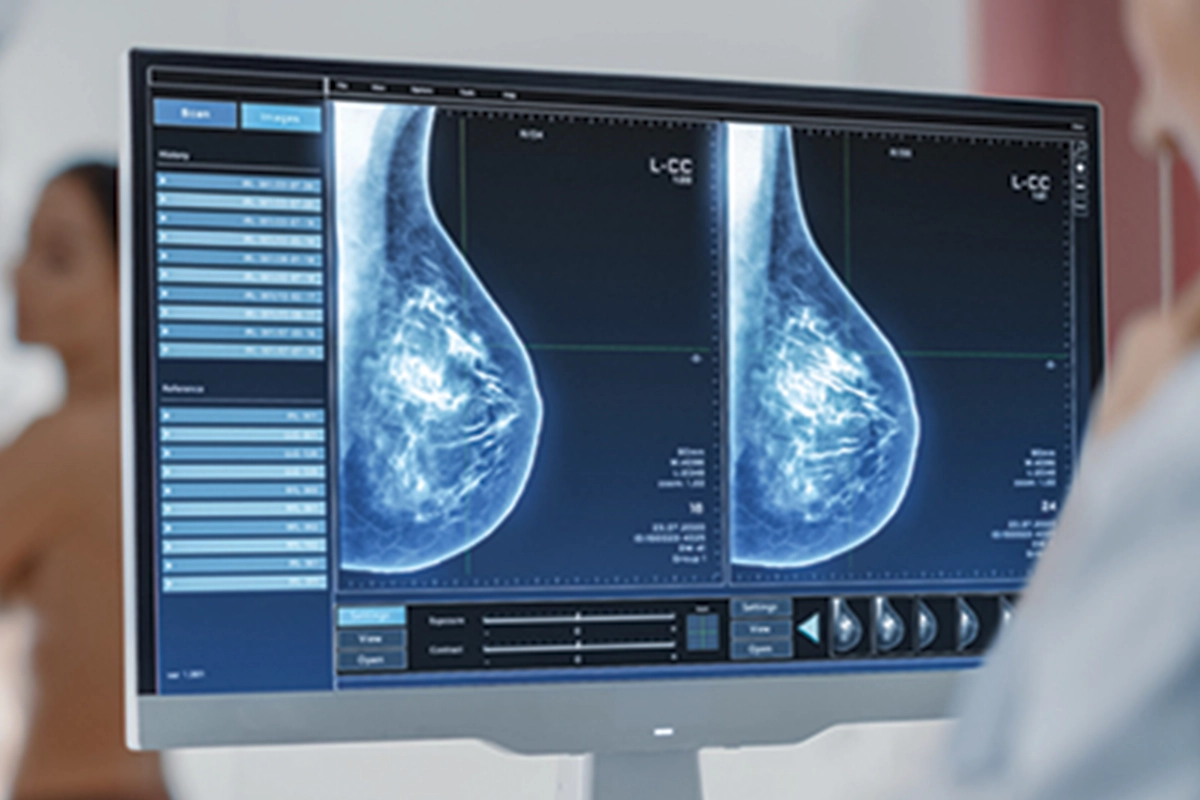

Meme kontrolünün nasıl olması gerektiğini anlatan Poçan, “Memedeki problemleri tespit etmek için yaş fark etmeksizin, kendi kontrollerimizi aksatmamalıyız. Kontrollerde bir problem tespit ettiğimizde ya da kırk yaş üstünde ise bir hekim tarafınca kontrol, meme ultrasonu, gereklilik halinde mamografi veya meme MRG ile tetkikleri gerekmektedir. Ülkemiz sağlık politikalarınca mamografi ön planda tutulsa da teknolojik gelişmelerin ultrason cihazlarında yapmış olduğu belirgin gelişim nedeniyle meme ultrasonu ile değerlendirme hem güvenilir hem de değerlidir” dedi.

Meme Ultrasonu, Mamografi ve Meme MR’ı hakkında da bilgiler veren Dr. Poçan, “Her üç yöntem de meme kanseri taramasında önemli rol oynar, ancak uygulama durumuna, hastanın özelliklerine ve risk faktörlerine göre tercih edilir” şeklinde açıklamalarda bulundu.